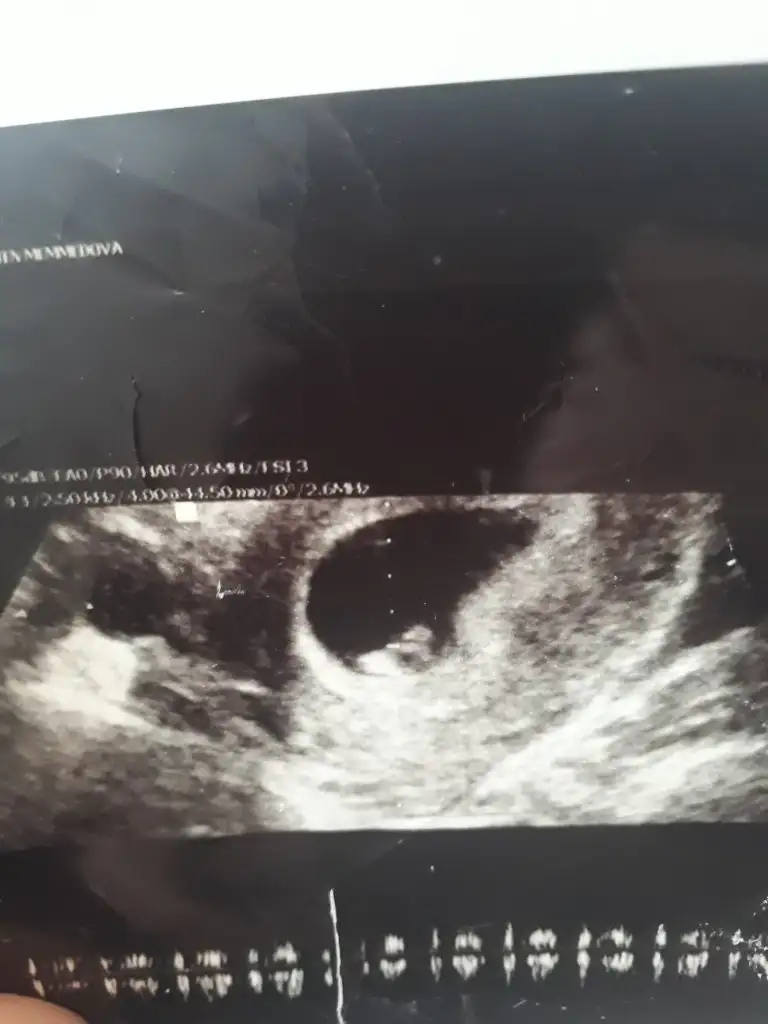

Erkek ve kız için 11 yada 12 hafta usg görüntüsü olmalı açıklamalar asagıda yazıyor 😊 rabbim herkesin gönlüne göre nasip etsin inşallah .. ecmain

[/B]Eki Görüntüle 473828 gordugunuz gibi ust taraftaki simgedende anlasildigi gibi eger cikinti paralel ise kiz

yok 30°lik bir aciyla yukari dogru bakiyorsa %99 oglunuz olacak demektir simdi bi kac ornek resimler daha koyacagim kiziminkide dahil

Eki Görüntüle 473831 simdi burada cikintilara bakin eger bel popo cizgisine paralel ise kiz

yok 30 derecelik bir aciyla yukari bakiyorsa erkek

yabancilarin hepsi biliyor bunu biz neden eksik kalalim gayet bilimsel simdi ellerinde11 12 13 ultrason fotografi olanlar alsin hemen baksin yada koyalim buraya yorumlayalim